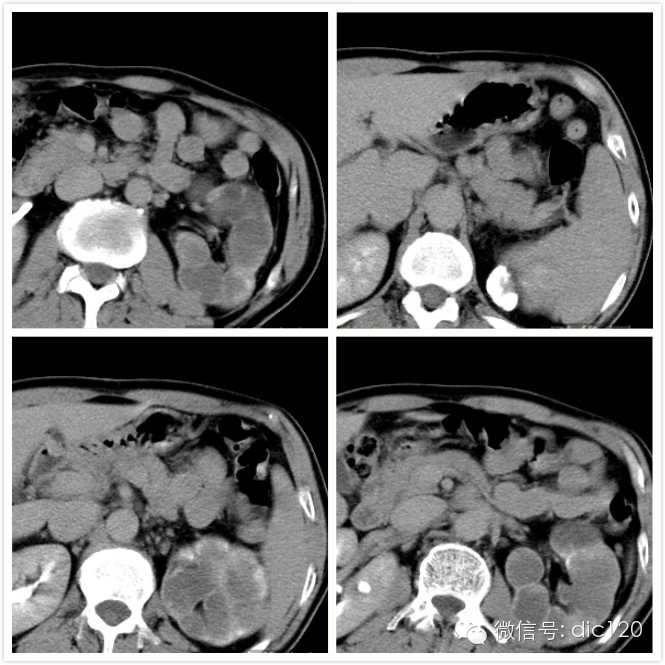

CT增强肾实质期图像

CT增强肾排泄期或肾盂期图像

CT图像特点:左侧肾盏、肾盂扩张,呈多发囊性低密度灶,囊内CT值略高于水;肾脏实质萎缩。 病变内可见结节状、云絮样子钙化灶,增强后未见明显强化。

④ 晚期肾脏体积缩小,形态不规则,肾盂肾盏壁明显增厚。